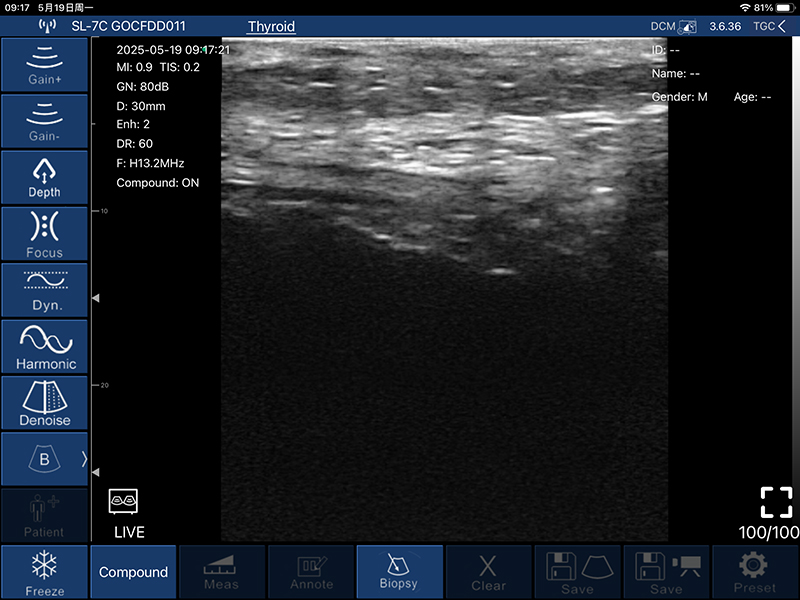

• 扫描深度:20/30/40/60mm,可调

• B模式

增益:30db-105db

降噪:0-1-2-3-4

动态范围: 40-50-60-70-80-90-100-110

• 图像调节:增益、焦点、

反相脉冲谐波、降噪

• 穿刺辅助功能:平面内穿刺引导线功能,平面外穿刺引导与血管自动测量功能